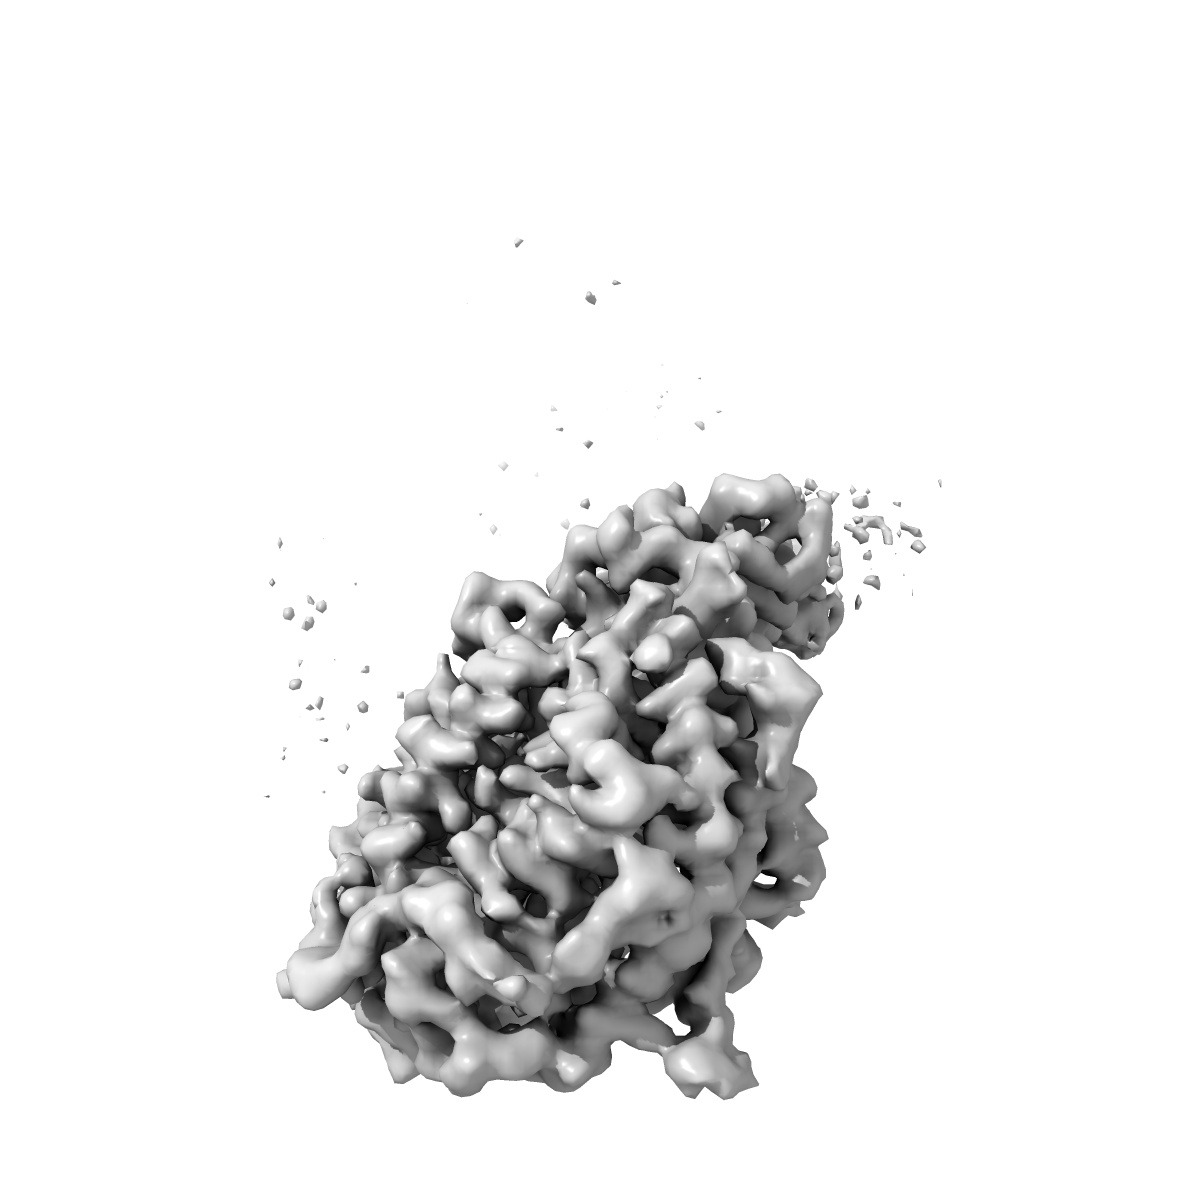

Cryo-EM structure of SARS-CoV-2 Alpha (B.1.1.7) spike protein in complex with human ACE2 (focused refinement of RBD and ACE2)

Single-particle3.04 Å

Sample: SARS-CoV-2 Alpha (B.1.1.7) spike protein in complex with human ACE2